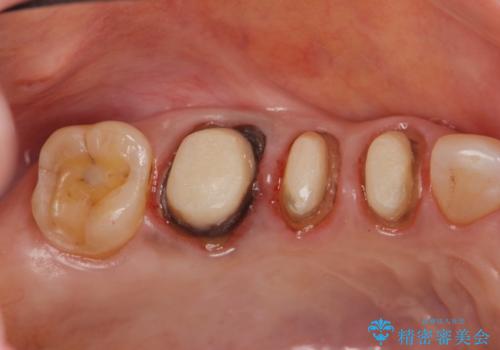

古くなったセラミッククラウンのやりかえ

- 老朽化し黒ずんできたクラウンのやりかえを希望され来院されました。

将来的に歯ぐきの位置が変化しても審美障害となりづらいオールセラミックジルコニアクラウンによるやり替えを計画します。

- 33万円(仮歯・ファイバーコア・ジルコニアクラウン×3)費用は治療当時の料金となります

金属を用いないクラウンんなので歯ぐきとの境目が黒くなる等の問題が起きません。